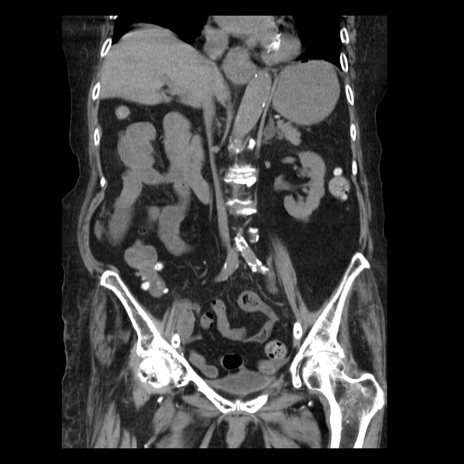

横断像

【症例】 90歳代女性

【主訴】 腹痛・嘔吐

【現病歴】今朝から左側腹部痛を認めた。 経過観察していたが、嘔吐を認めたため来院。

【既往歴】 子宮癌術後

【身体所見】 意識清明、BP 127/54mmHg、P 98bpm Sp02 95%(RA)、BT 35.8°C、腹部平坦・軟腸ぜん動音聴取良好、右下腹部圧痛(+) 反跳痛なし

【データ】WBC 9800、CRP 0.46